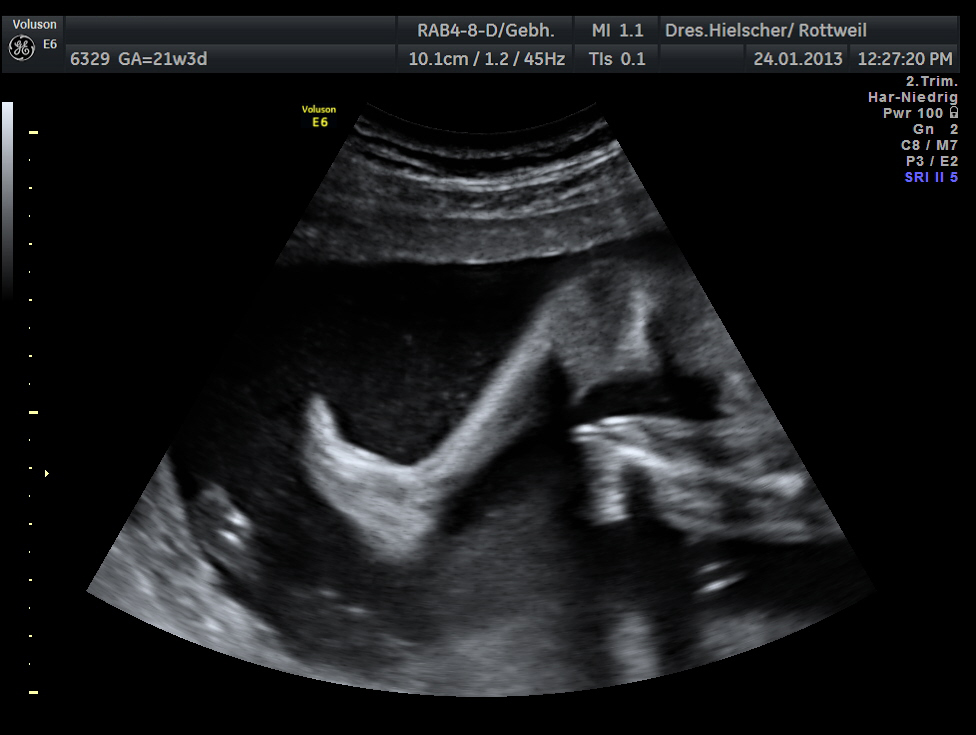

Feindiagnostik (ca 20. - 22.SSW)

Der Begriff Feindiagnostik beschreibt die ultrasonographisch subtile Suche nach Organfehlbildungen des Kindes in der 20.-21. Schwangerschaftswoche (sogenanntes Organscreening).